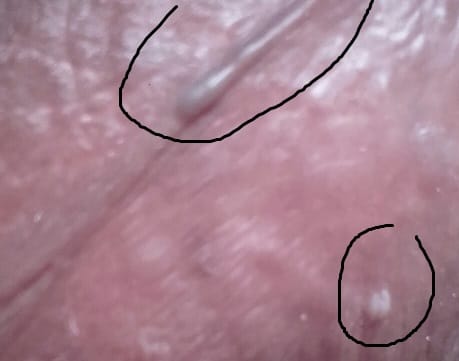

¿Es posible que esto sea herpes?

La verdad que esto me preocupa mucho, llevo un tiempo notando que me aparecen como pequeños gránulos que no me producen dolor ni nada por el estilo, ¿es posible que si me hago la circuncisión pueda deshacerme de estas cosas?